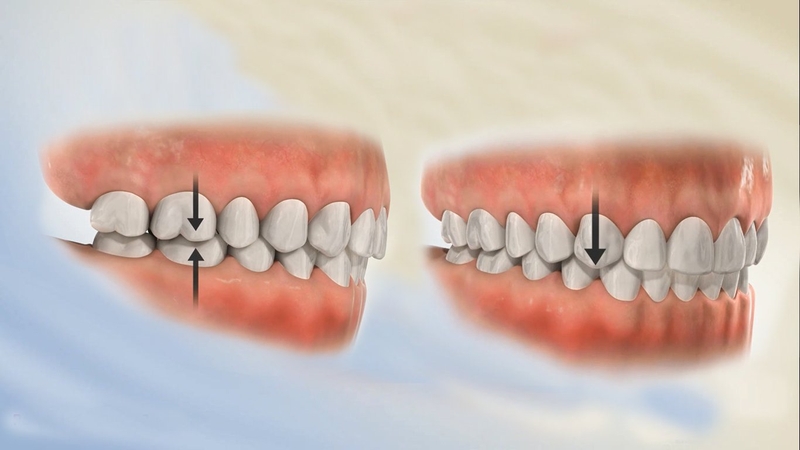

Gãy xương hàm dưới có thể dẫn đến tình trạng sai lệch khớp cắn